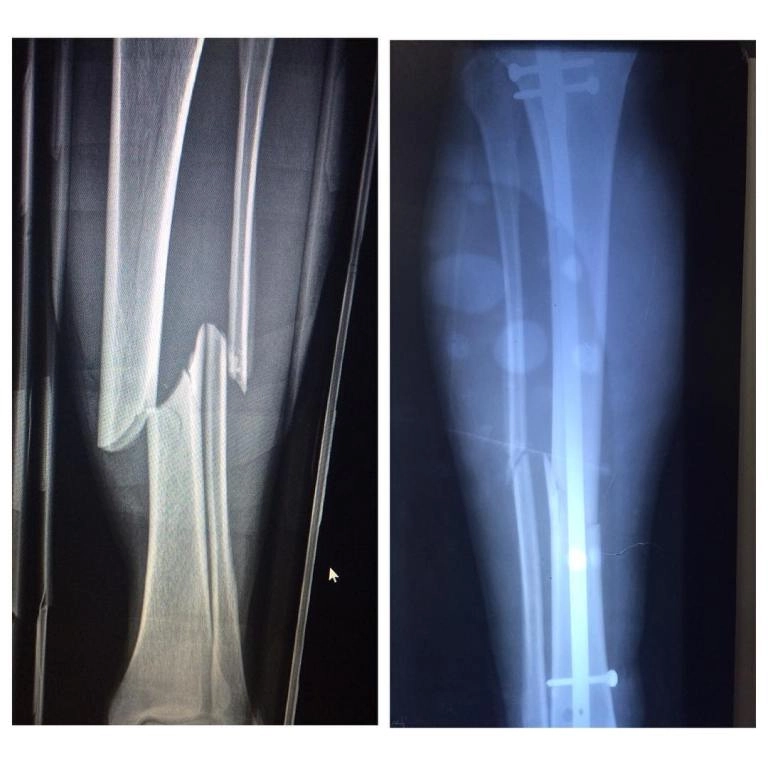

• Также востребованы процедуры по восстановлению связок, остеосинтез костей при переломах разной сложности.